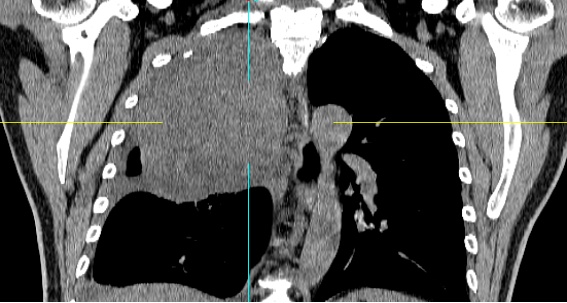

患者黄某因近3个月来反复咳嗽、久治不愈,前往当地医院就诊。检查结果让他和家人大吃一惊:右侧胸腔内竟长有一个巨大的肿块。胸部增强CT显示肿块大小约16cm×12cm,且与胸膜顶大血管关系极为密切。

正月初八,患者慕名来到郴州市第一人民医院东院胸部肿瘤外科就诊。接诊的胸部肿瘤外科主任马忠厦博士分析认为,患者肿瘤巨大,紧贴无名静脉及锁骨下动静脉,手术过程中稍有不慎便可能导致难以控制的大出血,甚至引发失血性休克或心脏骤停。这场手术,堪称在刀尖上起舞。